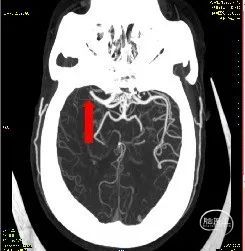

在CT室立即予以阿替普酶0.9mg/kg溶栓,同时完善CTA检查。

颅脑CTA:左侧颈内动脉闭塞、右侧大脑M1远端闭塞。

术前DSA

M1闭塞消失 溶栓后血栓移位?M2下干取栓?